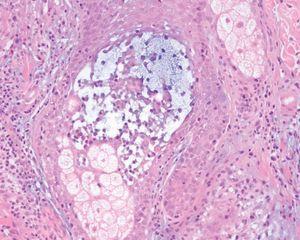

Varias biopsias cutáneas tomadas de distintas localizaciones presentaban, como característica común, la presencia de densos infiltrados linfocitarios dérmicos constituidos por células de tamaño pequeño-interme-dio con núcleos hipercromáticos y cerebriformes con marcada tendencia a la distribución perifolicular y ocasionales linfocitos que infiltraban el epitelio folicular (fig. 2). Algunos folículos se acompañaban de mucinosis folicular (fig. 3). Destacaba la presencia de densos infiltrados linfocitarios, semejantes a los perifoliculares, que se localizaban en íntimo contacto con los ovillos ecrinos con infiltración ocasional del epitelio ductal (fig. 4).

Fig. 3.—Detalle de la mucinosis folicular. (Azul Alcián pH 2,5, ×200.)